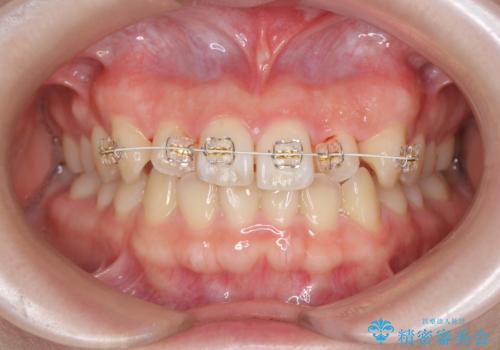

- ねじれの目立つ前歯を改善したいと、矯正治療を希望され来院されました。

インビザラインの不得意な上顎前歯のねじれの改善を、マウスピース矯正を行う前に前歯のみの部分ワイヤー矯正を行うことで治療期間の短期化を目指します。

上顎前歯のねじれはマウスピースで治りづらいため、マウスピース矯正の治療期間の長期化をきたしやすい歯列不正です。

マススピース矯正を始める前に、部分ワイヤー矯正を行うことで治療の短期間化・良好な仕上がりを達成することができました。